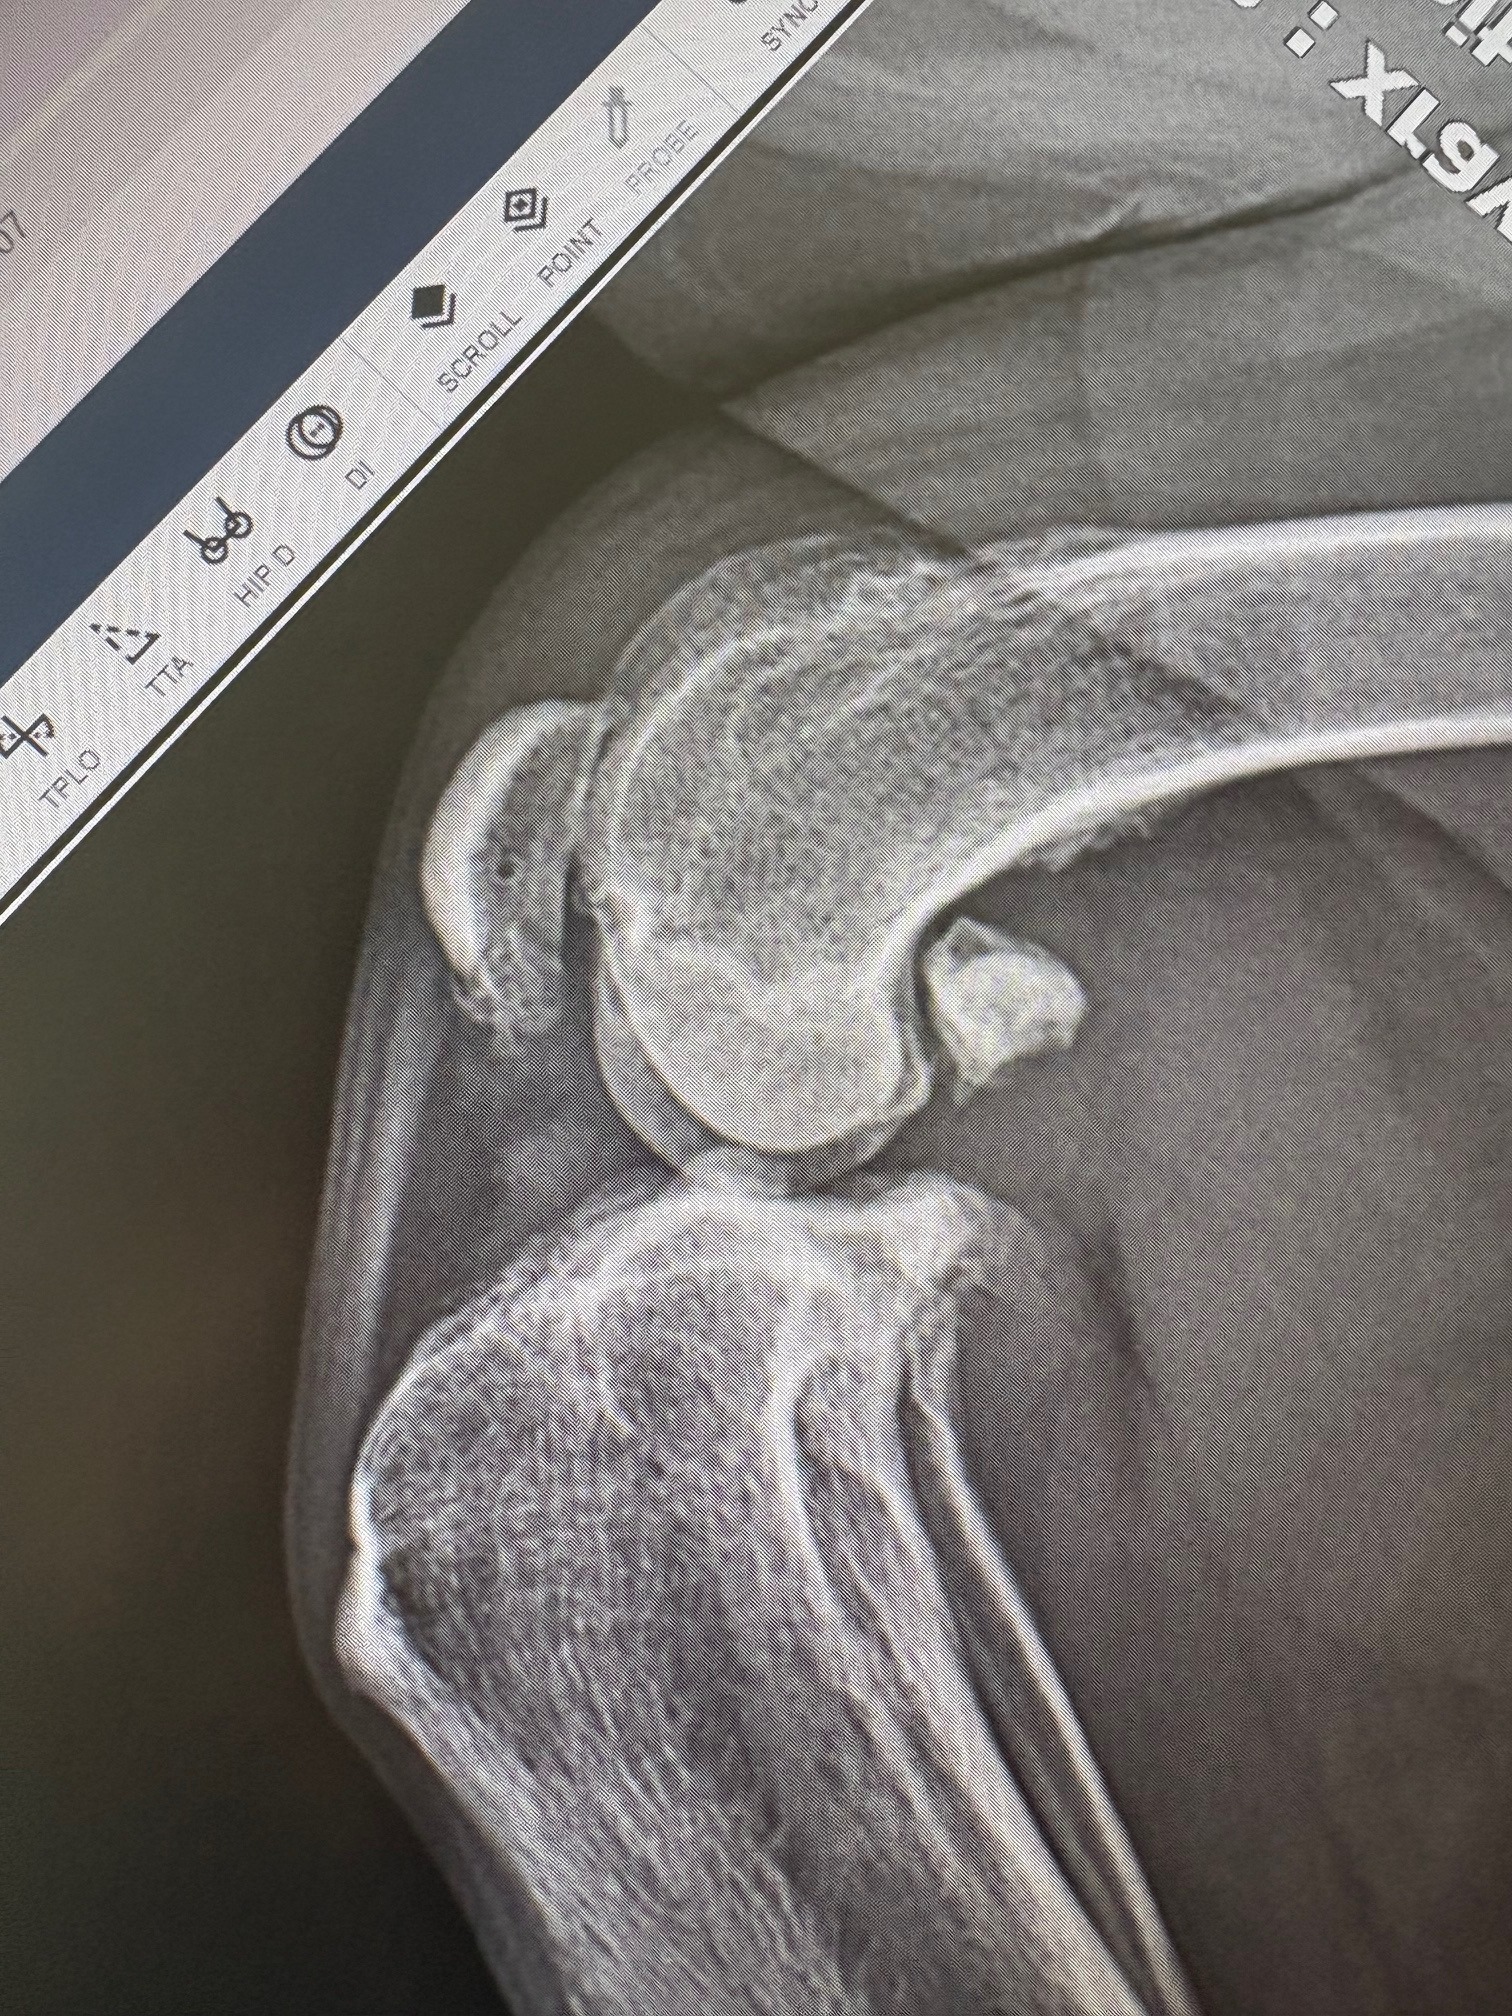

In August 2024, my sweet Loo tore the ACL in her right back leg - a painful and debilitating injury for dogs. The ACL (anterior cruciate ligament) keeps the knee stable, and when it tears, every step is a struggle. She needed an extensive surgery that cost around $7,000. It was a tough hit financially, but there was never a question - we had to help her. With the help of my amazing parents, who I’m so grateful for, we made it happen.

For a while, she did great and was on the road to recovery. But just a few months later, she started limping again - this time on her other back leg. Our vet suspected the same injury, but at the time, X-rays didn’t show a full tear. We’ve done everything we can over the past year to keep her comfortable and happy.

Now, almost a year later, her pain has come back, this time worse. New radiographs have confirmed what we were afraid of - her left ACL is torn, and she needs surgery as soon as possible. Watching her struggle to simply walk breaks my heart. She’s only seven and still has so many adventures ahead of her - giving up is not an option.